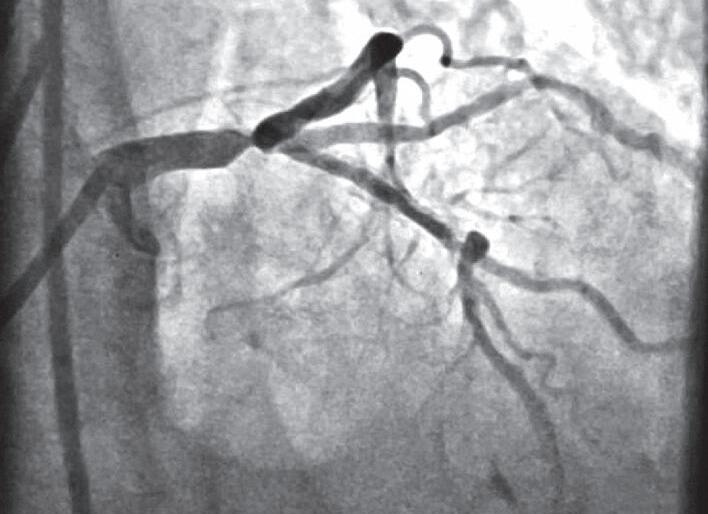

E. Escore CRUSADE baixo indica baixo risco de eventos isquêmicos em 30 dias

23. (Título de Especialista em Cardiologia) Observe o caso clínico a seguir: Paciente do sexo masculino, de 58 anos de idade, obeso, sedentário, apresenta quadro de dor precordial típica que surgiu em repouso, associada a sudorese e mal-estar. Ao exame físico: paciente dispneico, boa perfusão periférica, estertores crepitantes nas bases pulmonares, ausculta cardíaca normal, pressão arterial (PA) = 100 × 60mmHg, frequência cardíaca (FC) = 120bpm. O eletrocardiograma (ECG) e a angiografia de coronária estão apresentados na Figura 3.23. Com base nesses dados, assinale a alternativa que apresenta os achados encontrados:

A. Infradesnivelamento do segmento ST em parede inferior – lesão proximal na coronária direita

B. Supradesnivelamento de aVR – lesão em tronco da artéria coronária esquerda

C. Infradesnivelamento do ST em parede inferior –lesão proximal em artéria descendente anterior esquerda

D. Supradesnivelamento de aVR – lesão proximal na artéria descendente anterior esquerda próxima da bifurcação

E. Infradesnivelamento do segmento ST em parede inferior – lesão proximal em artéria circunflexa dominante